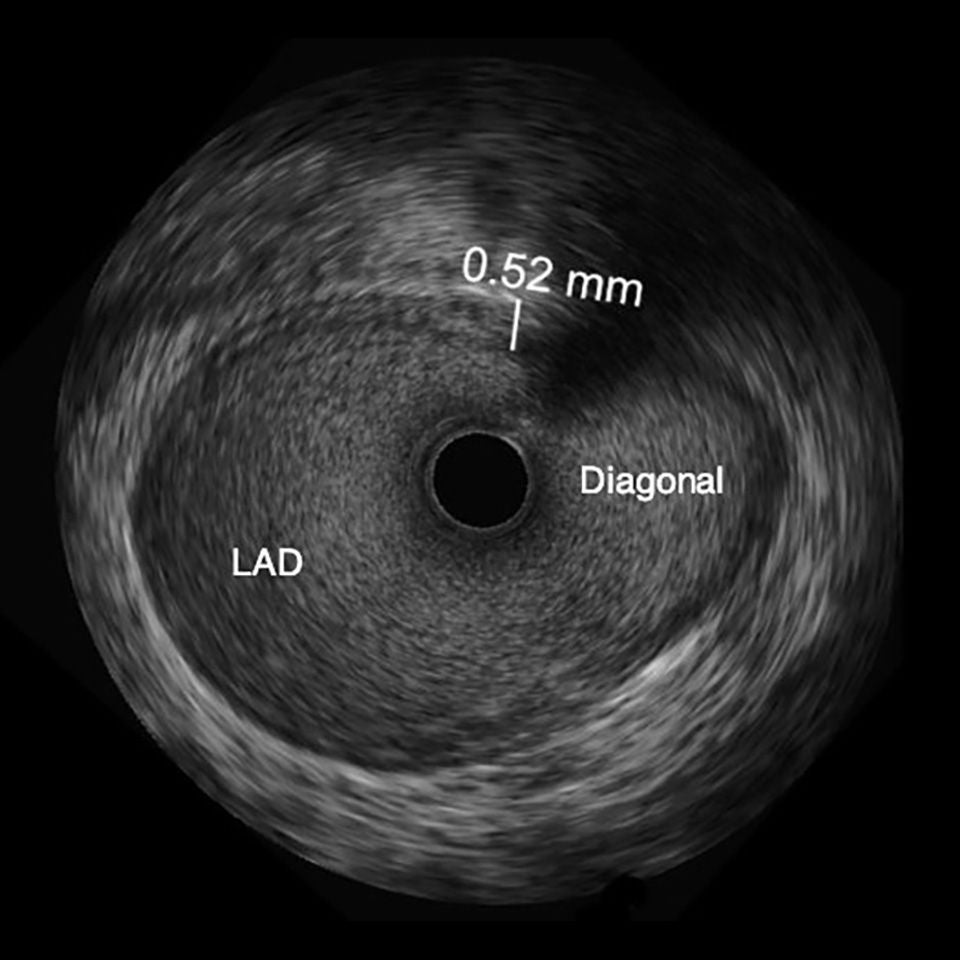

OPTICROSS HD Imaging Catheter 60 MHz

High-definition IVUS image of inside a coronary lesion using the OPTICROSS HD catheter